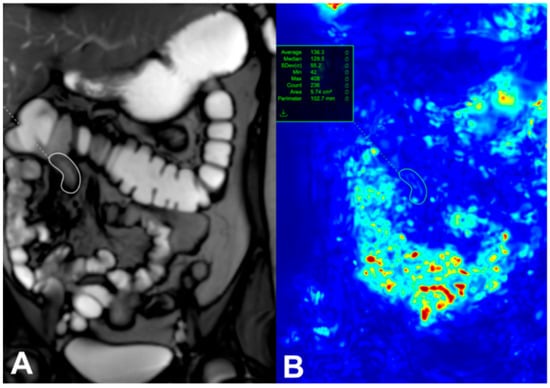

Patients with active CD are known to have reduced intestinal motility, which can be measured using cine sequences. The mechanisms behind decreased motility in CD-affected bowel are multifactorial, involving fibrotic and inflammatory infiltration, neuritis within the bowel walls, and systemic effects of inflammation through neuronal and hormonal pathways. Advances in MRI technology now allow for the capture of small-bowel motility in a single breath hold, and post-processing software can quantify this motility, as shown in Figure 1 [8]. This figure was taken from Figure 6 of Rimola et al.’s study [8].

Figure 1. A single image from a dynamic set with a region of interest (white circle) placed on a diseased terminal Ileum (A). Motion is assessed by assigning each pixel in the image an associated displacement value and is expressed as a quantitative value (green circle) (B) [8]. This figure was taken from [8].